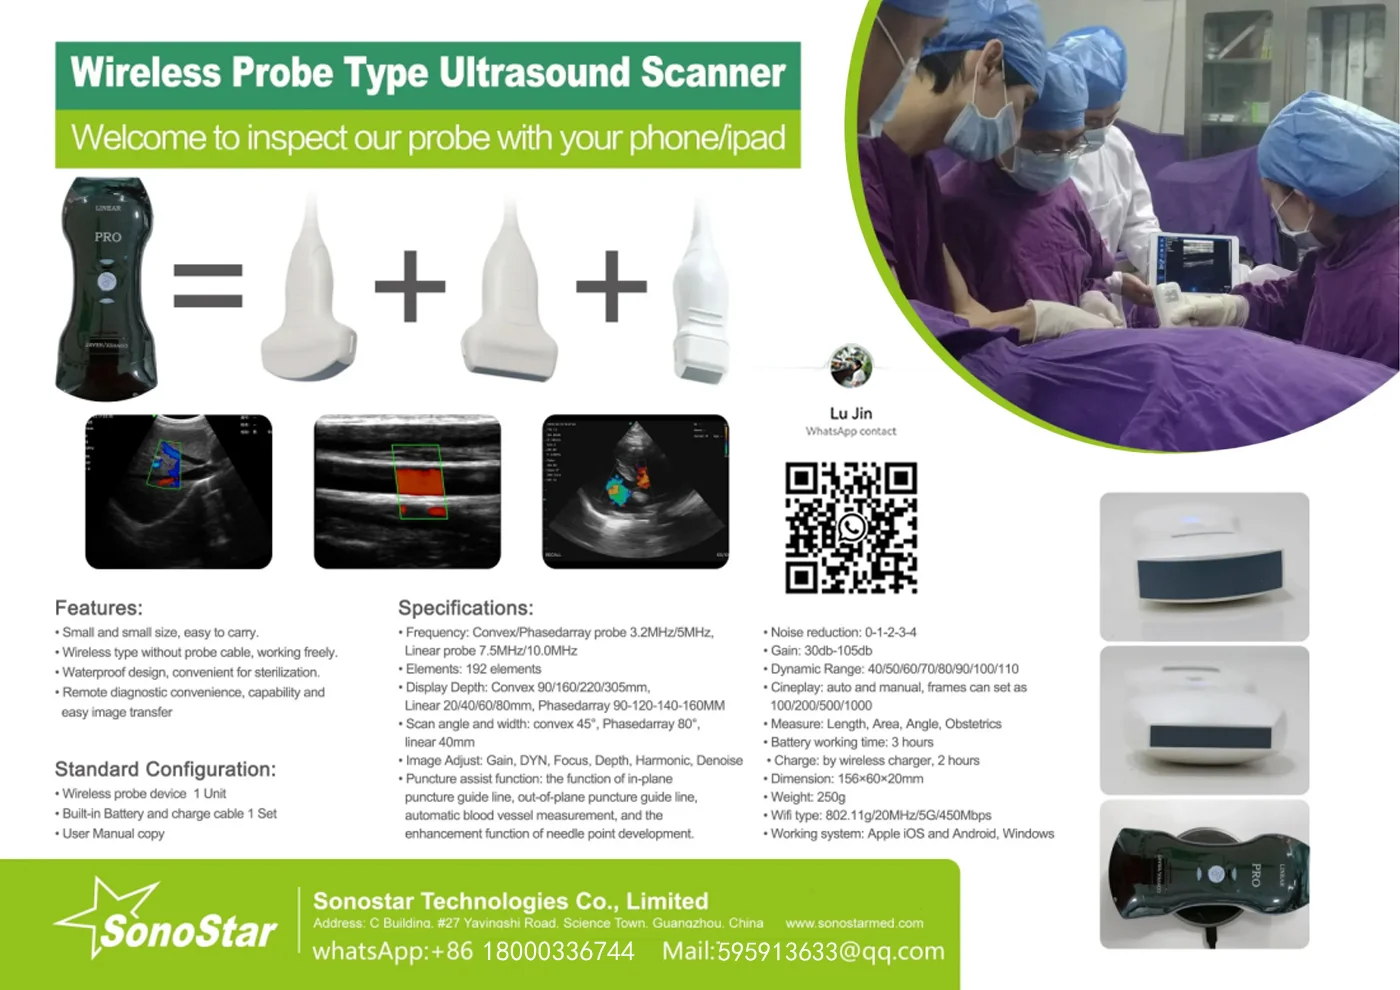

Small Full Digital Portable Ultrasound Equipment with Android/IOS Windows

Convex Probe Parameters

-Scanning system: array sweep

-Frequency: 3.5MHz

-Probe element: 80

-Depth: 90-200mm

-Host:

IOS: IPAD mini/IPAD air/IPHONE etc.

Android: Smartphone/pad, Samsung, HTC, Sony, Huawei, LG etc.

Windows: windows 10 system

-Connection: 802.11.g WIFI(AP)

-Throughout: 54Mbps

-Field of view: 80 degree

-Display mode: B,BM

-Image gray scale: 256 level

-Gain:30-105Db

-Measure: distance, area, obstetrics and other

GA(CRL),GA(BPD),GA(GS),GA(FL),GA(HC),GA(AC)

-Language: English, Russian, Italian, Spanish, Chinese, Portuguese

-Power: by built-in battery

-Power consumption: 10W (probe run) /2W (probe stop)

-Battery last: 3 hours

-Footprint: 156mmx60mmx24mm

-Weight: 308 g

Linear Probe Parameters

-Scanning mode: Electronic array

-Display mode: B, B/M

-Probe element: 80

-Channel of RF circuit board: 16

-Frequency: 7.5MHz/10MH

-Scan depth: 20/40/60/100mm

-Head width: 40mm

-Image Adjust: BGain, TGC, DYN, Focus, Depth, Harmonic, Denoise, Color Gain, Steer, PRF

-Cineplay: auto and manual, frames can set as 100/200/500/1000

-Puncture assist function: the function of in-plane puncture guide line, out-of-plane puncture guide line, automatic blood vessel measurement.

-Measure: Length, Area, Angle, heart rate, Obstetrics

-Image save: jpg, avi and DICOM format

-Image frame rate: 18 frames / second

-Battery working time: 3~5 hours(according to different probe and whether keep scan)

-Battery charge: by USB charge or wireless charge, take 2 hours

-Dimension: 156×60×20mm

-Weight: 220g~250g

-Wifi type: 802.11g/20MHz/5G/450Mbps

-Working system: Apple iOS and Android, Windows 10 system

Standard Configuration:

-Main Host(probe) 1 Unit

-Internal Battery and charger 1 Set

-Non-slip lanyard